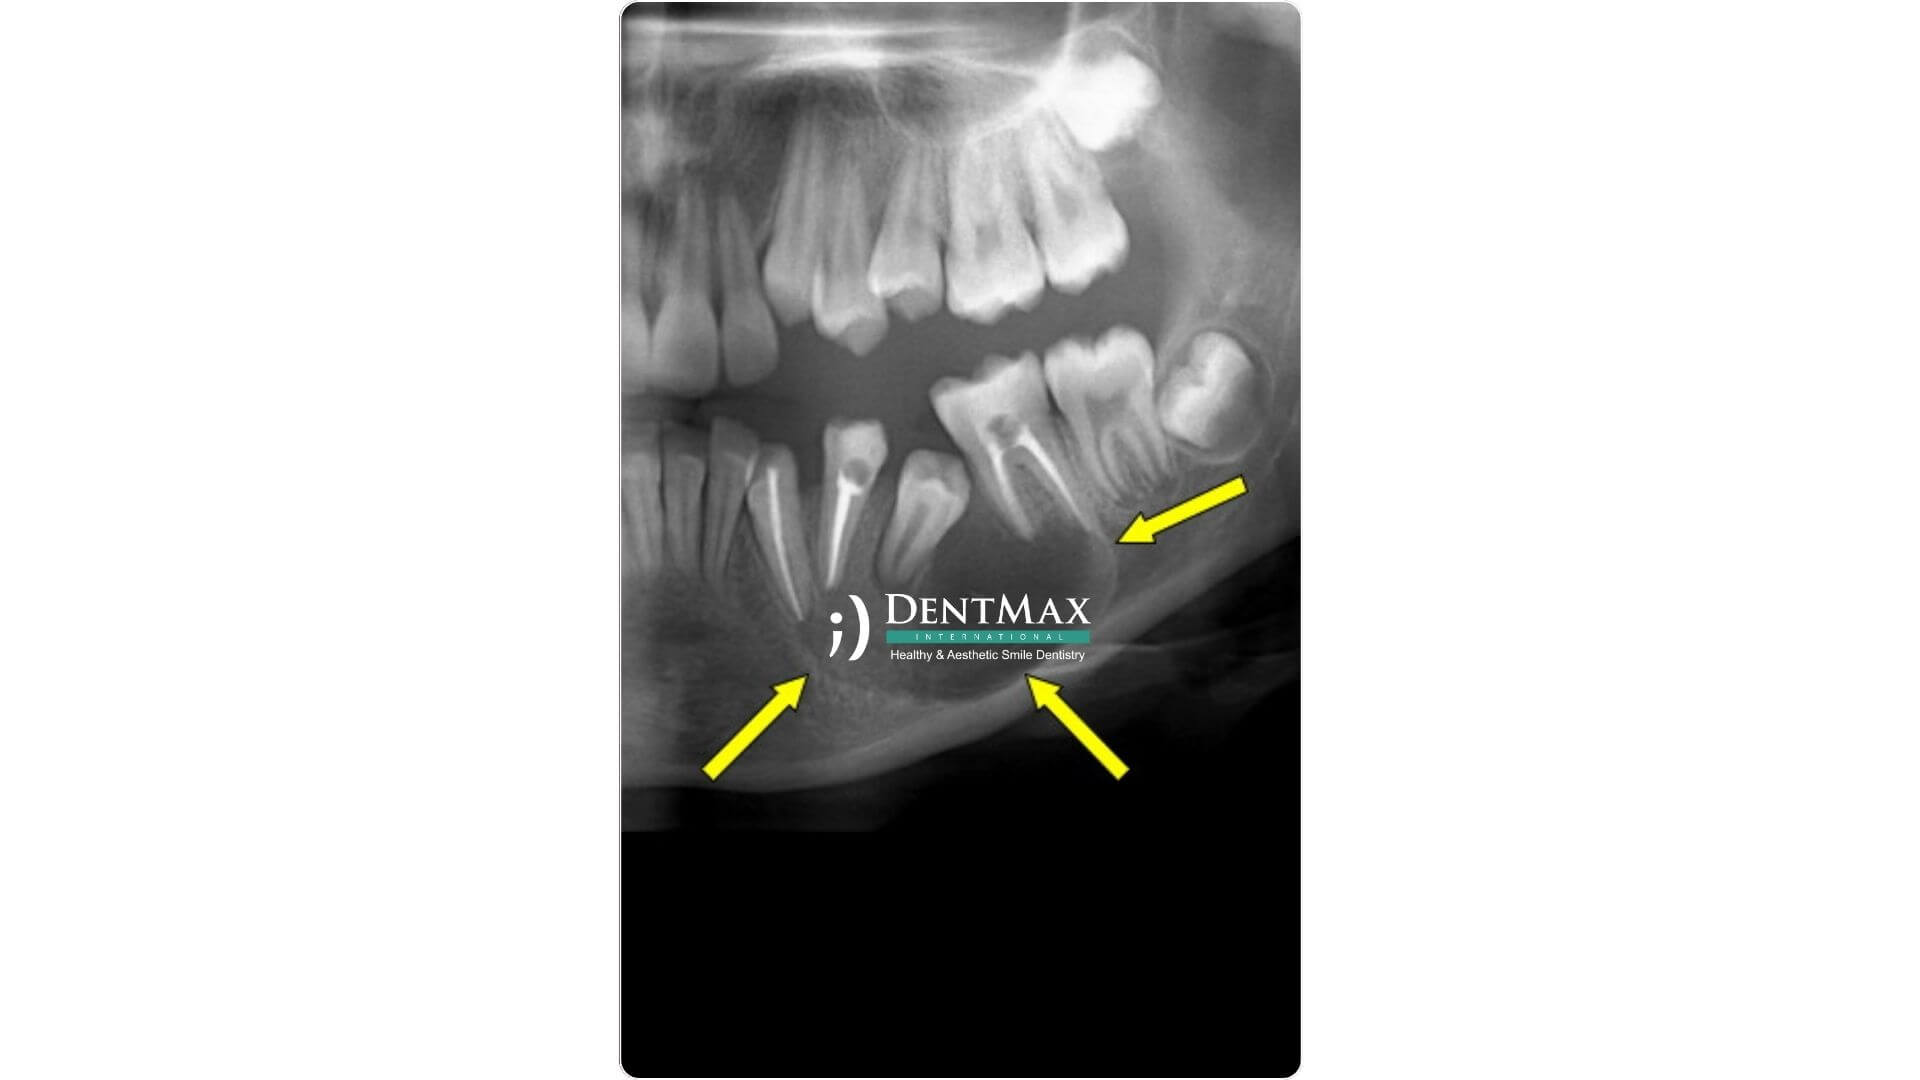

Tanı genellikle panoramik röntgen (OPG) veya 3D dental tomografi ile konur. Diş kistinin yeri, büyüklüğü ve çevre dokulara etkisi detaylı şekilde değerlendirilerek tedavi planlaması yapılır.